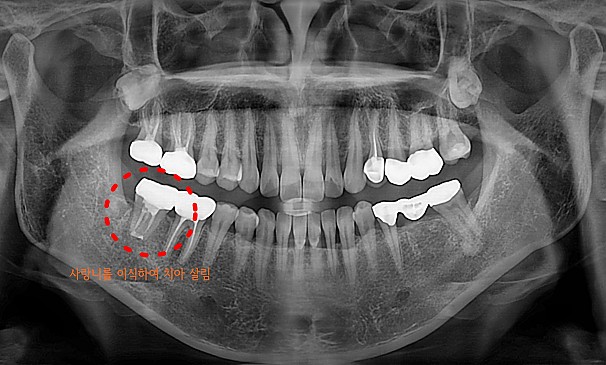

자가치아이식술

박OO님 전후사진 | 치료 기간 : 1주

치료 전

치료 후